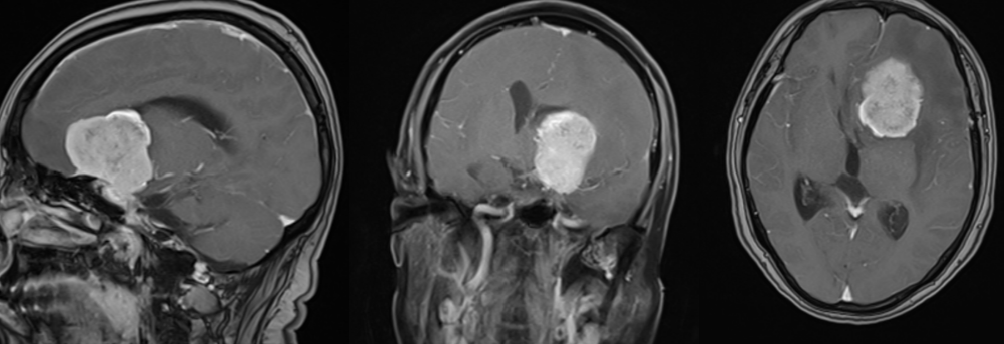

术前核磁增强检查:

图2

入院后我院援疆专家赵明飞主任带领神经外科团队针对患者病情进行分析,入院后检查、结合患者影像学特点、查体及既往病史,初步考虑患者颅内病变为巨大功能区脑膜瘤。需及早行手术切除肿瘤,以缓解肿瘤对神经纤维束的压迫,减少对功能区脑组织损伤,积极争取使患者肢体功能最大恢复。此患者脑肿瘤位于右侧大脑功能区,开颅手术过程中若损伤功能区脑组织,将会造成永久性不可逆的神经功能缺损,出现肢体活动障碍。赵明飞主任应用神经导航联合术中黄荧光成像技术完成肿瘤的精准切除,完美保护脑功能。手术顺利结束。术后月热尼沙的头痛症状随即就得到了改善,肢体功能无影响,复查头部CT及MR提示脑肿瘤完整切除,效果满意。